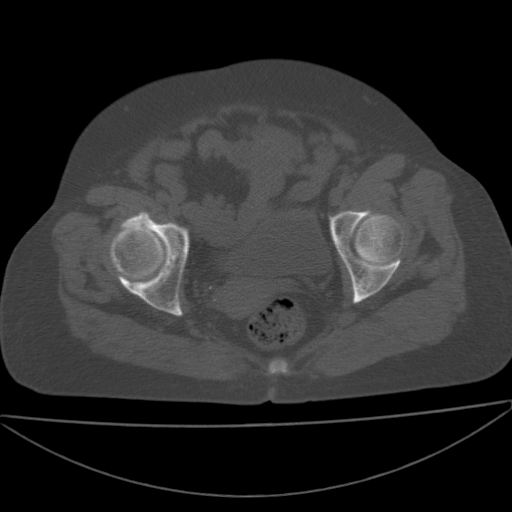

以下是引用王显瑞在2009-4-23 16:45:00的发言:[br]考虑股骨颈陈旧性骨折,股骨头缺血型坏死

以下是引用余辉在2009-4-23 17:08:00的发言:[br]考虑右髋关节退行性变.股骨颈改变考虑陈旧性骨折可能,股骨头顶部关节面下似有透亮区,股骨头皮质环增厚,考虑有股骨头坏死